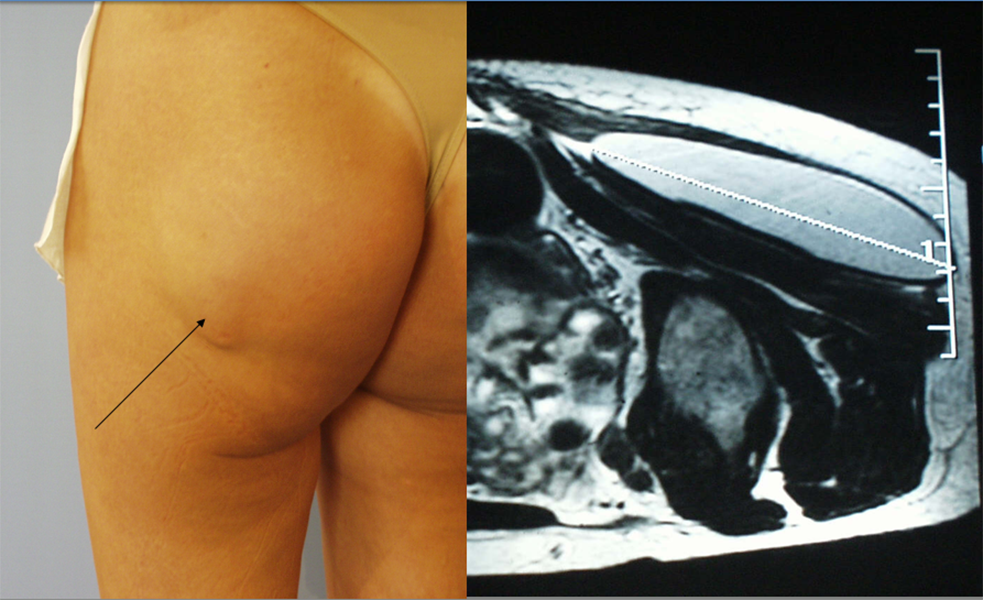

Implant placed too close to the skin surface

specific contra indication